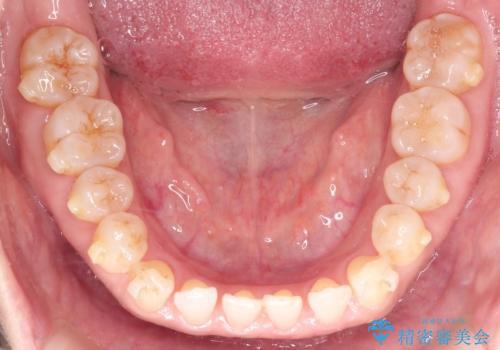

前歯の隙間 インビザラインによる目立たない成人矯正

- 前歯の隙間を気にされて来院されました。

インビザラインにて、目立たずに矯正治療を行うこととしました。

歯と歯の間にある隙間を閉じるのは、インビザラインでもしっかり治療できます。